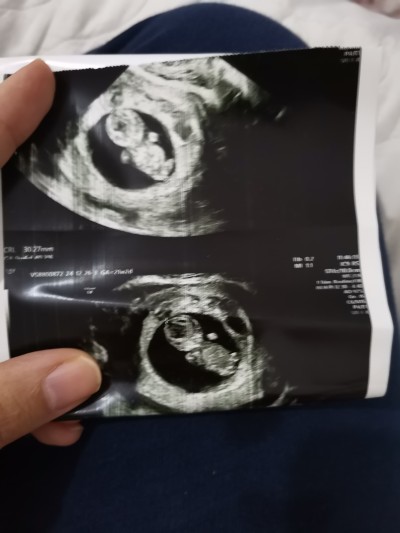

Kafa Yapısına Göre Kese Şeklini Tahmin Etmek Mümkün mü?

kese seklıne göre kafa yapısına göre tahmin yuruten varmı hanımlar

Niyeyse ilk başta erkeğe benzettim canım

Bende erkeğe benzettim çünkü erkek bebeklerde erkenden eli kolu belli oluyor